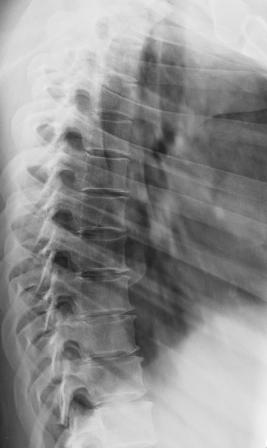

A

Image A shows our patient's lateral thoracic spine radiograph, performed for back pain. The spine is very washed-out in appearance and hard to see due to marked osteopenia. A normal comparison in a different patient is shown in Image B, where each vertebra and disc space can be clearly seen. Radiography cannot quantify the degree of bone loss, but can detect overall decreased density as well as comlications, like compression fractures. For quantification, bone densitometry is indicated.